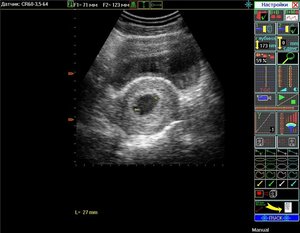

Морула - це всього лише 32 клітини вашої майбутньої дитини, але вони активно розвиваються, і до кінця 3 тижня вагітності ваша дитина буде схожа на кульку діаметром всього 0,2 мм з числом клітин рівним 250 (медики назвуть вашу дитину - бластоциста). У цей час ендометрій матки вже підготувався до прийняття вашої дитини (бластоцисти) і тут починає відбуватися фізичне злиття мами і майбутньої дитини - відбувається імплантація. Після імплантації харчуванням майбутнього малюка починає займатись ваш організм.